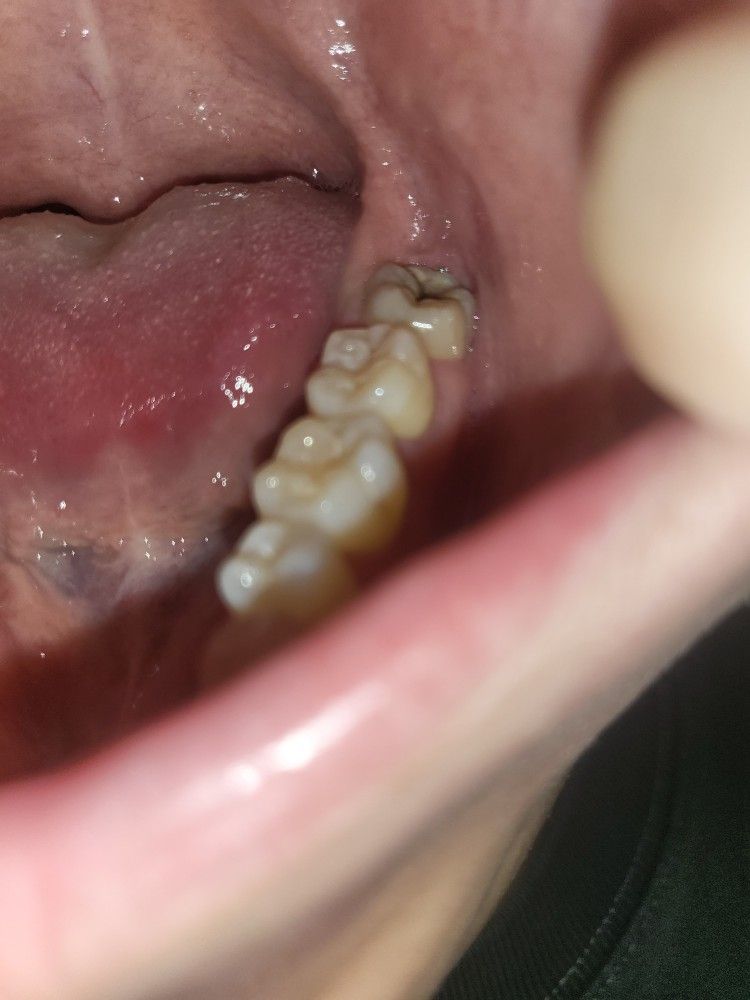

사랑니 발치 질문합니다. 엑스레이 사진 첨부해서요 ?

교정을 위해 사랑니를 뺴려고 합니다... 찾아보니 사랑니는 잇몸을 쨰고 뺴면 마취 풀린후 통증이 매우 심하다고 다들 그러네요..

저는 잇몸을쨰고 빼야하는지 궁금합니다. 나이는 25살 남자입니다.

이미 사랑니가 나와 있는 상황에서는 잇몸을 절개하지 않고 발치가 가능합니다.

잇몸을 절개 하지 않고 발치를 해되 될것같습니다. 크게 통증이 잇을 사랑니는 아니니 너무 걱정하지마세요.